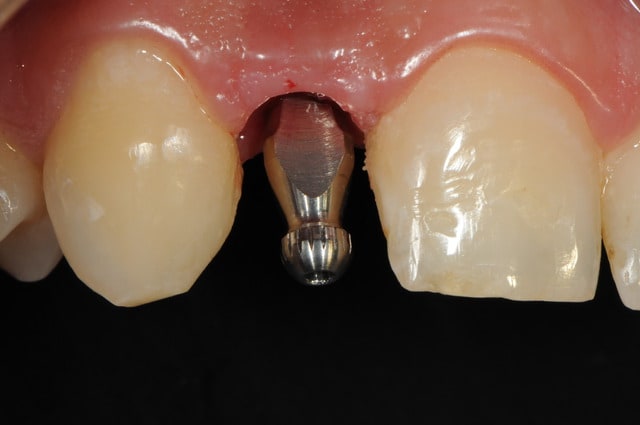

-cicatrisation de la première vis de cica,

-diamètre plus gros pour la vis de cica

- pilier pour la provisoire

- provisoire moule ION

- ajustage

- polissage soigneux

la suite tout à l'heure, ça sonne à la porte...